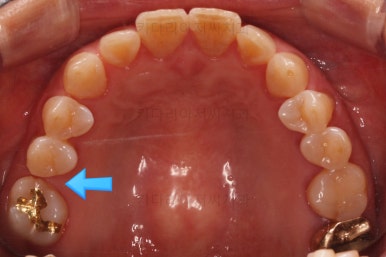

초진 때의 사진입니다.

전반적으로 치열이 삐뚤하고 불균일한 양상이긴 하지만 꼭 이런 부분들까지 교정을 해야 하는 건 아니에요.

부산교정치료 전후사진을 비교해 보겠습니다.

쓰러진 치아도 원위치로 만들어 기능을 회복시켜주었고, 임플란트도 1개로 마무리를 할 수 있었어요.